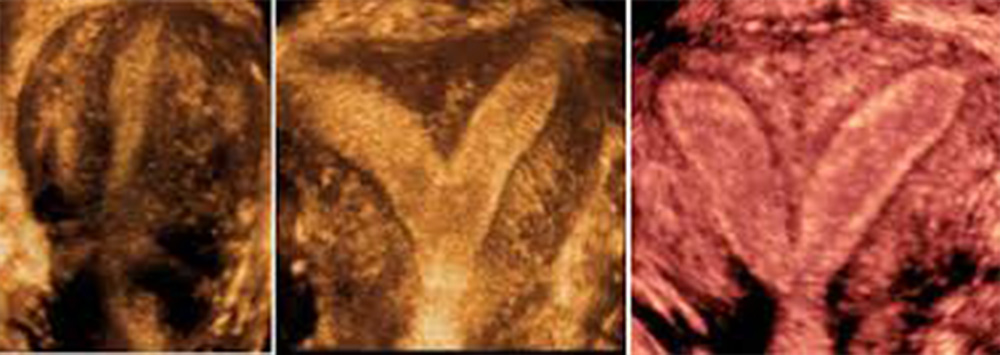

Η έγχρωμη τρισδιάστατη υπερηχογραφία (3-DPD), είναι μία αναβάθμιση του έγχρωμου Doppler, απεικονίζοντας το αγγειακό σύστημα στις τρεις διαστάσεις, με φόντο μια γκρίζα κλίμακα, που απεικονίζει μαλακούς ιστούς, δίνοντας έτσι εικόνα παρόμοια με αυτή της αγγειογραφίας, αφού επιτρέπει την άμεση απεικόνιση των πολλαπλώς αναδιπλούμενων αγγείων και τη σχέση τους με παρακείμενους ιστούς και όργανα. Με τη χρήση της τεχνικής αυτής, επιτελείται μελέτη της αρχιτεκτονικής της μικροκυκλοφορίας του όγκου και διαχωρίζονται οι όγκοι σε καλοήθεις και κακοήθεις, αφού θεωρείται ότι η ύπαρξη ακανόνιστης αγγειακής διάταξης με πολύπλοκη ή μη γεωμετρική διακλάδωση με διασκορπισμένα αγγεία συνηγορεί υπέρ κακοήθους εξεργασίας.

Η τεχνική (3-DPD) αποτελεί μια απαιτητική διαδικασία από μαθηματικής και τεχνολογικής απόψεως, που βασίζεται στην αλληλεπίδραση από την ανακατασκευή της γεωμετρίας των αγγείων, χρησιμοποιώντας ευκρινείς εικόνες που λαμβάνονται από μικρές περιοχές του όγκου, με αποτέλεσμα τη μέγιστη διαγνωστική ακρίβεια.

Επομένως, η χρήση του (3-DPD) επιτρέπει την εκτίμηση φυσιολογικών, παθοφυσιολογικών και αιμοδυναμικών μεταβολών στο σώμα της μήτρας, τις ωοθήκες και στους μαστούς μέσω της εκτίμησης του φαινομένου της αγγειογένεσης.